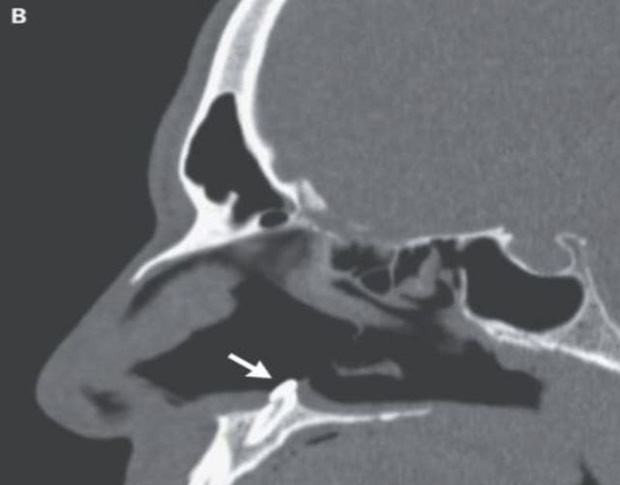

Tuy nhiên, các bác sĩ đã sớm phát hiện ra có một vật cứng nằm sâu bên trong lỗ mũi và phát hiện ra đó là một chiếc răng đang mọc bên trong khoang mũi.

Về mặt y học, người đàn ông có một "chiếc răng mọc ngược" mọc trong mũi. Răng lệch lạc là tình trạng răng mọc không đúng vị trí, rất hiếm gặp.